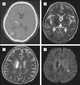

Hemiparesis, or unilateral paresis, is weakness of one entire side of the body (hemi- means "half"). Hemiplegia is, in its most severe form, complete paralysis of half of the body. [Source: Wikipedia ]